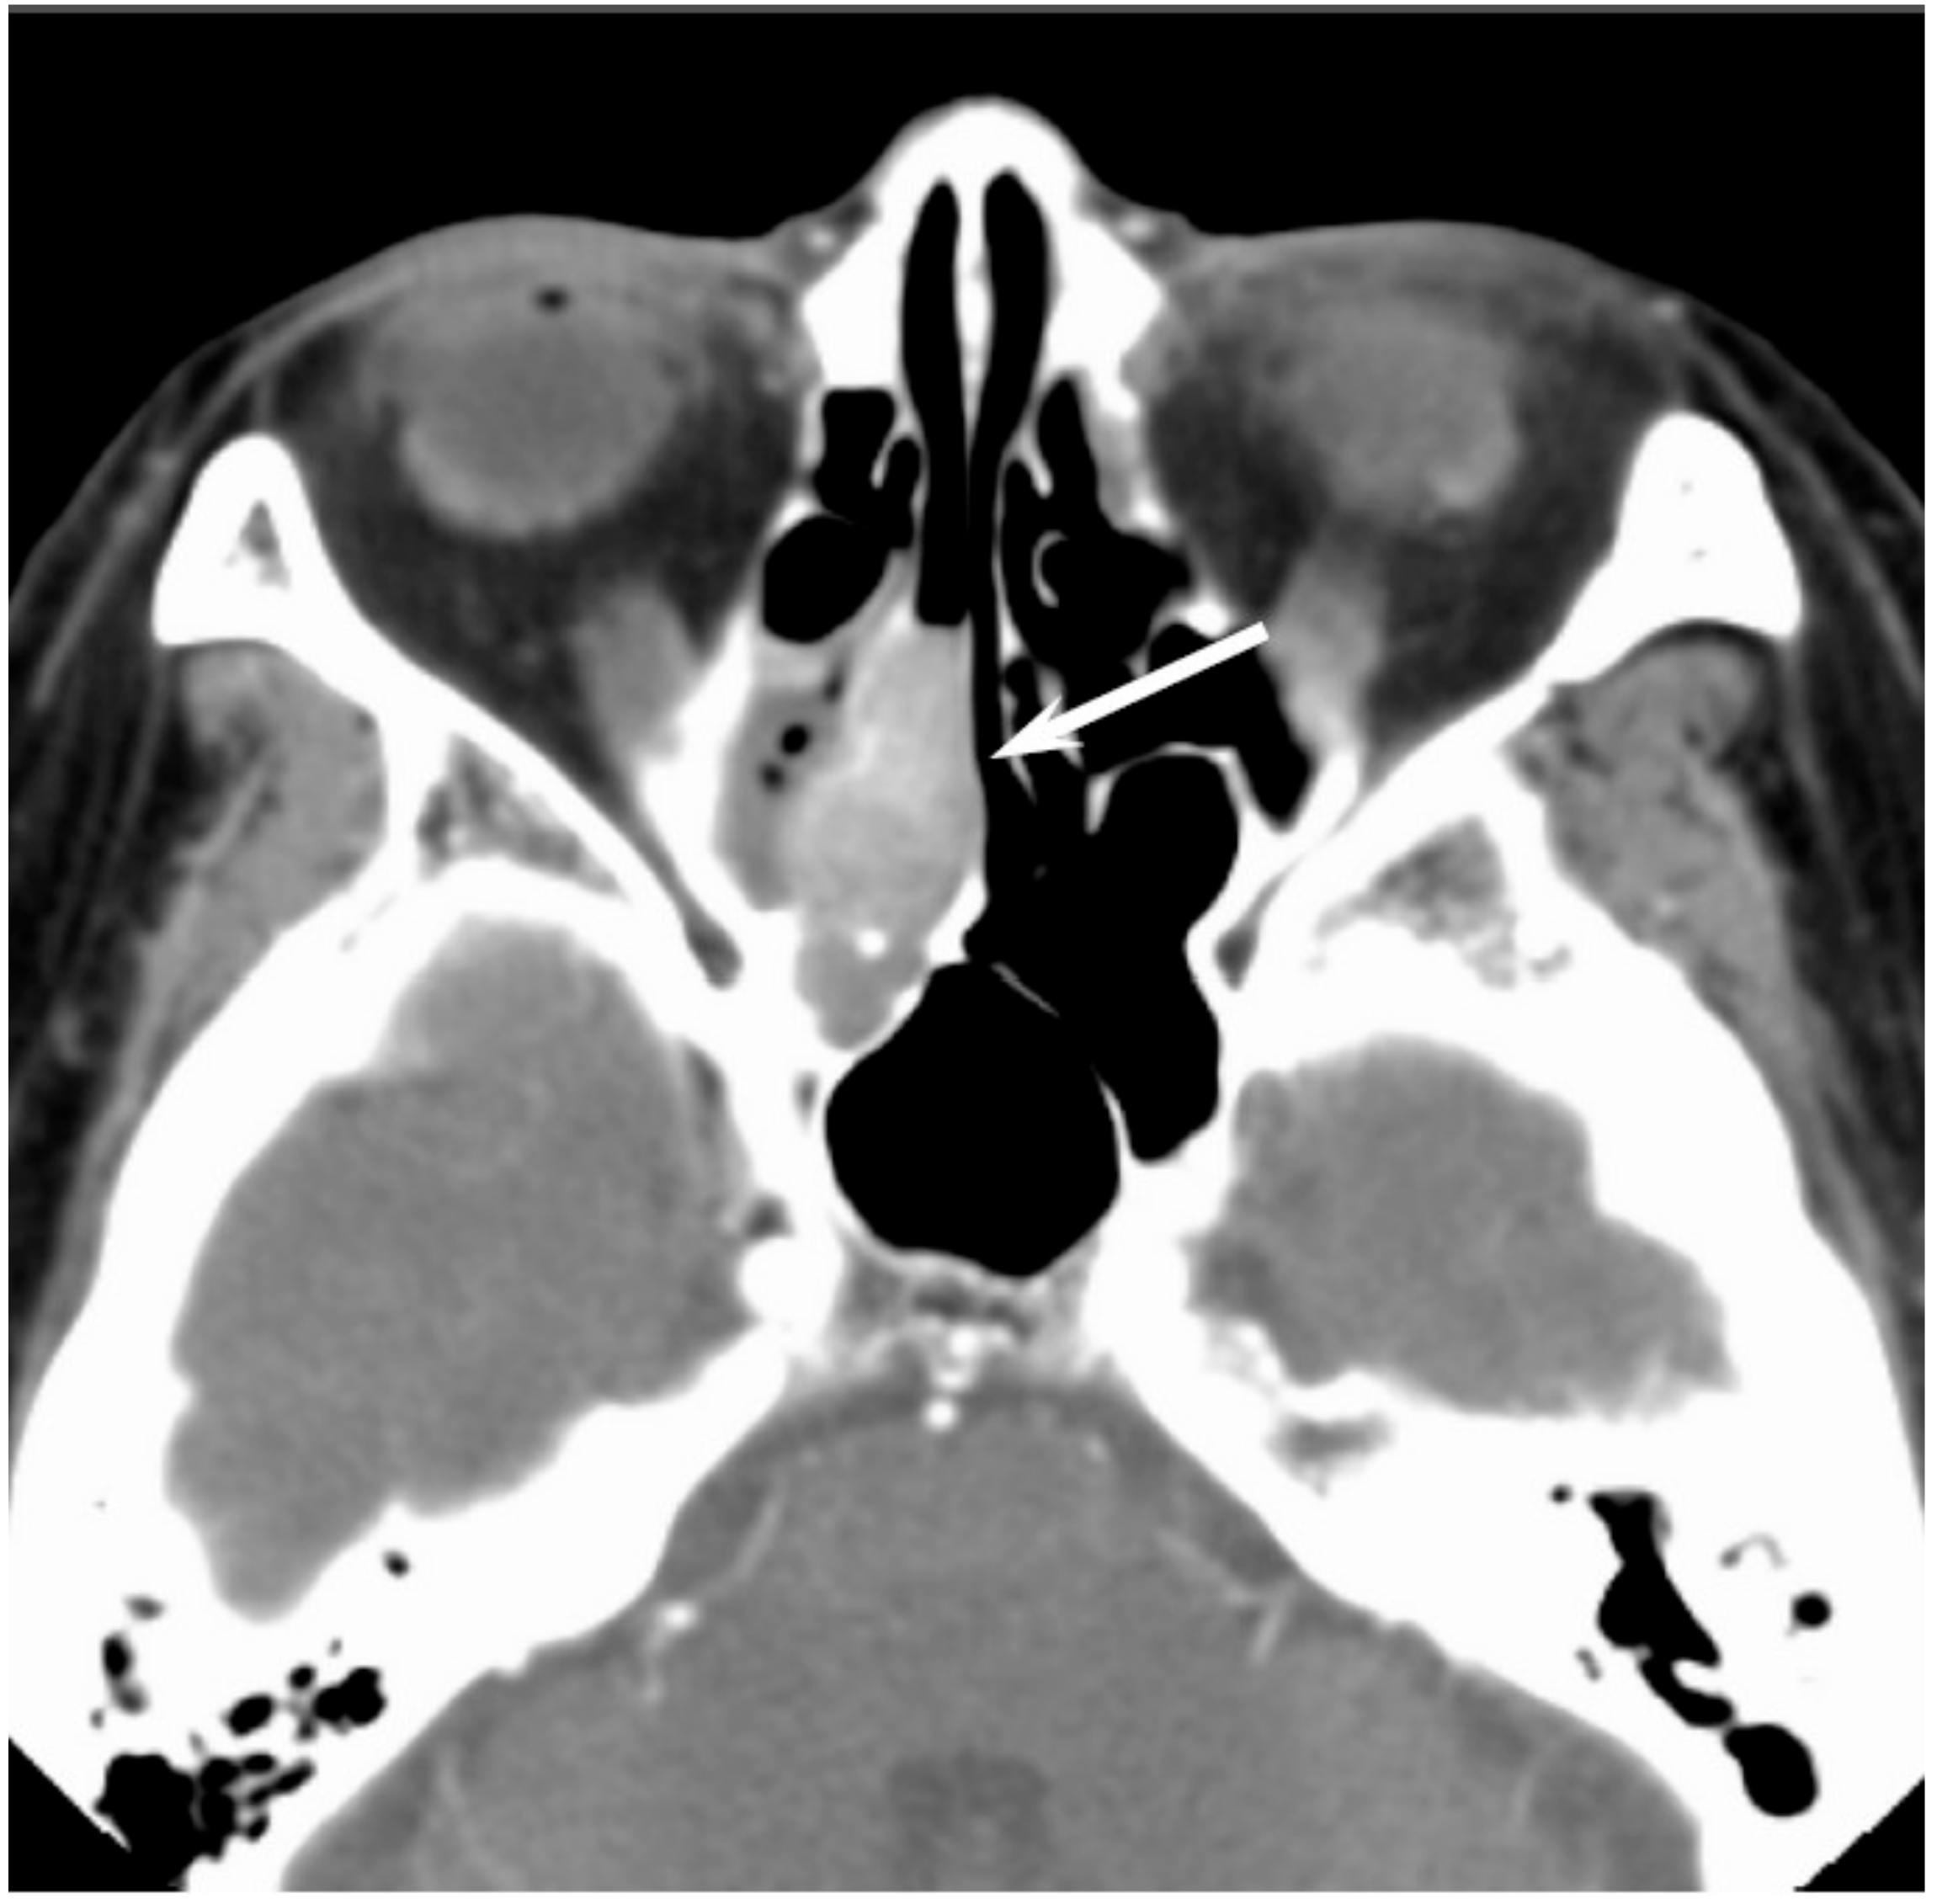

CT findings are nonspecific; however, CT is useful for the evaluation of the remodeling of the the surrounding bone or bony erosion [36]. On T1WI, sinonasal MMs that contain melanin or hemorrhage usually show iso- to hyperintensity relative to the gray matter; however, amelanotic melanoma may also show hypointensity (Figure 8). T1 shortening more often appears as a reflection of the paramagnetic effects associated with the products of hemorrhage rather than the presence of melanin [37]. On T2WI, sinonasal MMs typically show hyperintensity relative to the gray matter; however, melanotic melanomas may show iso- to hypointensity. MMs typically show a heterogeneous strong contrast enhancement owing to the rich vascular network.

Figure 8. Malignant melanoma of the right nasal cavity. T1-weighted image showing heterogeneously hyperintense areas within tumor (arrow).